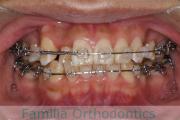

- ≫治療中 ステップ1

-

上顎

下顎

前歯の関係など

右側

正面

左側